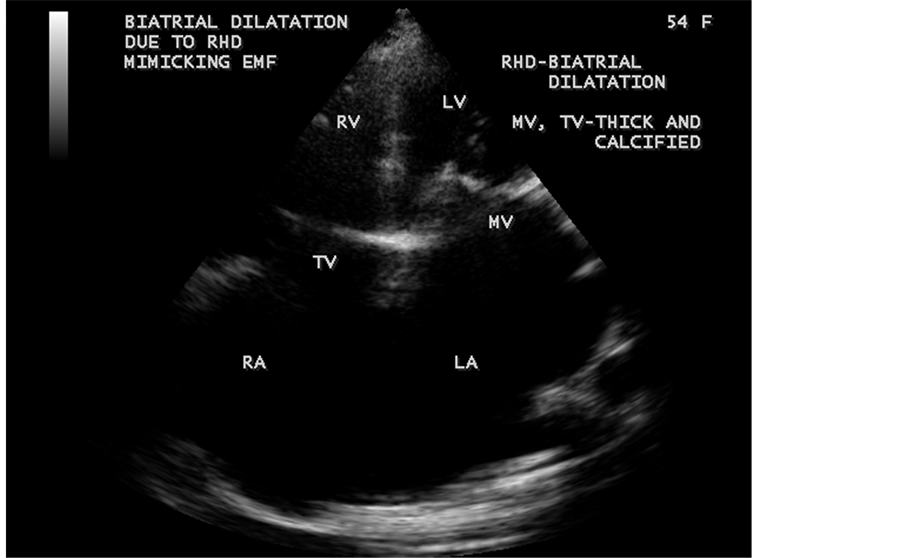

Figure 56. Biatrial enlargement in a 54-year-old female due to rheumatic AV (atrioventricular― mitral, tricuspid valves) involvement mimicking biatrial enlargement due to EMF as shown in Figure 33.

Figure 57. Biatrial enlargement due to rheumatic AV (atrioventricular) valve stenosis (mitral stenosis, tricuspid stenosis)―in contrast to EMF as shown in Figure 34 which is associated with AV valve regurgitation.

Figure 58. Showing the rheumatic tricuspid stenosis and tricuspid regurgitation jets in a 54-year- old female.

Figure 59. Showing the severe rheumatic mitral stenosis jet in a 54-year-old female.

ventricle”) in a 16-year-old female as shown in Figure 50 to Figure 53 were detected. RV EMF with rheumatic involvement of mitral valve as shown in Figure 54 and Figure 55 in a 44-year-old female and in Figure 63 in a 55-year old female. Biatrial enlargement due to rheumatic atrioventricular (AV) valves (mitral and tricuspid) involvement characterized by stenosis of the valves are illustrated in Figure 56 to Figure 59 in a 54-year-old female and it is differentiated from EMF which is characterized by AV valve regurgitation as shown in Figure 34 and Figure 60. RV EMF associated with thickening and fibrosis of moderator band in a 16-year-old female was shown in Figure 46. RV EMF associated with apical left ventricular hypertrophic cardiomyopathy was shown in a 47-year-old male as in Figure 61 and in a 65-year-old female as in Figure 62.